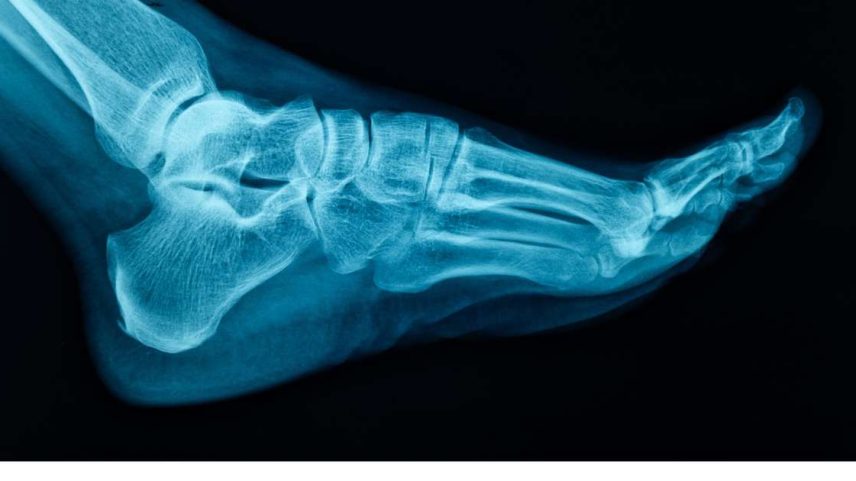

Ortopedista alerta sobre riscos de traumas e desgaste nos pés

Ortopedista alerta para traumas, desgaste e joanetes; calçados inadequados elevam riscos à coluna e à mobilidade, com cirurgias cada vez mais precisas

As intervenções cirúrgicas na região do pé são, em sua maioria, motivadas por traumas, desgastes e condições adquiridas, como o joanete e o pé plano

A cada 25 anos de vida, a média de caminhada de uma pessoa chega a 40 mil quilômetros, equivalente a uma volta ao redor do mundo. Esse dado reforça a necessidade de cuidados com os pés e membros inferiores para evitar lesões que impactem o bem-estar geral. O ortopedista José Antônio Veiga Sanhudo destaca fatores de risco comuns: traumas domésticos, lesões esportivas e acidentes de trânsito.

Entre as principais causas de problemas na região, o desgaste natural das articulações aparece pelo impacto repetido das caminhadas ao longo do tempo. O especialista, que também atua no desenvolvimento de dispositivos médicos, afirma que o uso de calçados inadequados é um vilão para a saúde ortopédica, podendo provocar dores nas pernas e na coluna.